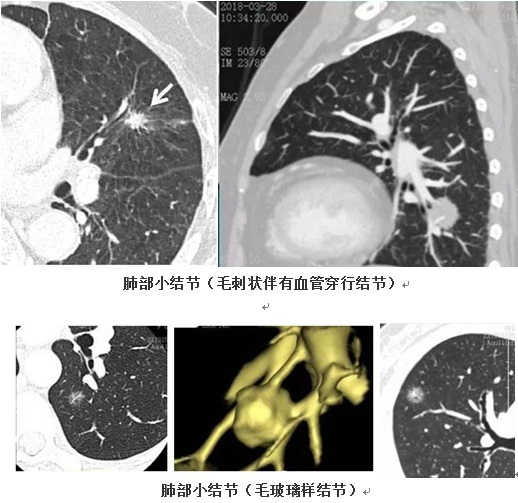

这个在体检单上“吓倒”不少人的肺部小结节,其实是通过肺部CT检查发现的,直径在10 mm左右的结节病变。肺部小结节多为体检时偶然发现,大多无典型症状,分布于肺内的各个部位,多为单个、亦有多发的情况。

4、检出的肺结节大小在10 mm左右,影像学上是否伴有血管穿行、伴有毛刺样、空泡征、分叶状或毛玻璃样改变,胸膜是否伴有凹陷或牵拉征象,或者定期检查结节不断增大等。